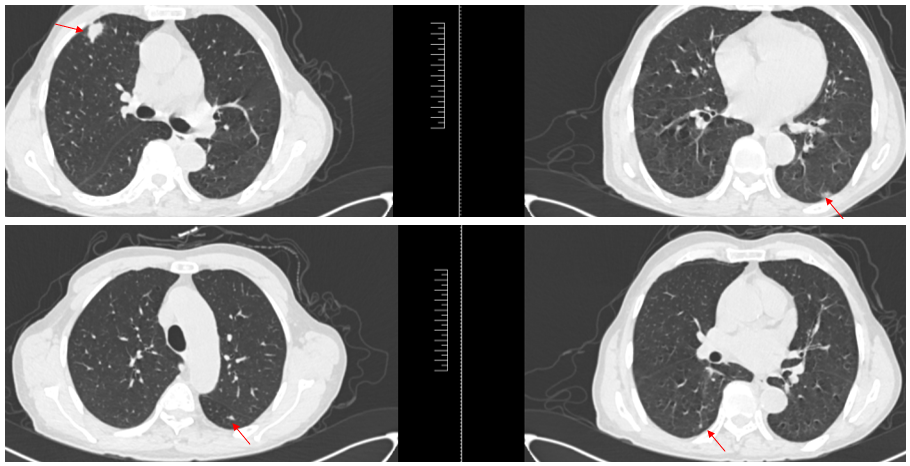

患者于2024年7月19日复查,胸腹CT检查提示双肺多发结节,考虑转移(图3)。穿刺病理证实为肠癌转移。

基因检测:KRAS G12V突变,HER2(2+)。